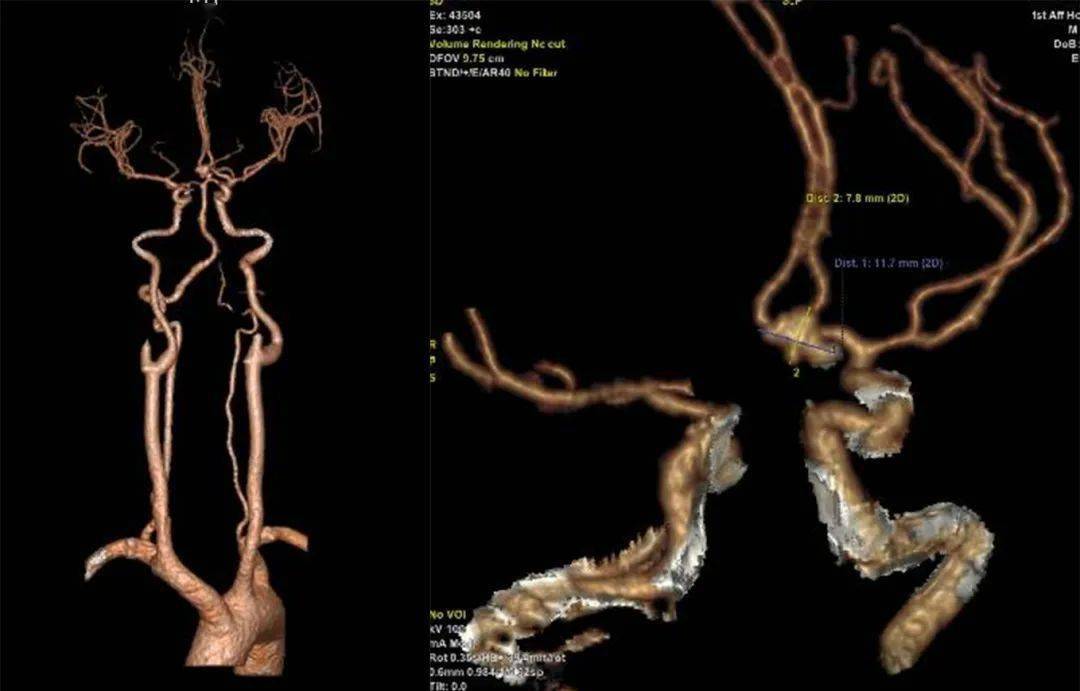

术前头部cta示大脑中动脉走形分支区域见增粗动脉血管影,局部呈结节状

(术前颅脑cta)